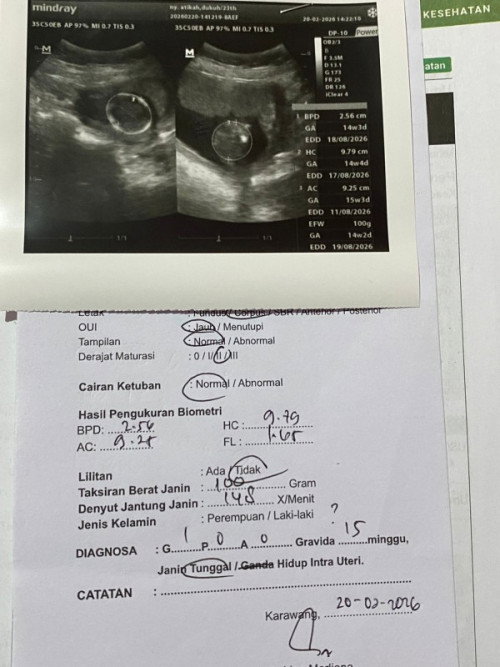

Aku masih tm2. Tapi, baru tadi pagi bangettttt. Shock, kok ada air di payudara ku??? ku pencet dikit, malah ada yg keluar dikit😭🙏 Tolong dibantu jawab bun. Aku anonim, krna malu, takut ada temen di apk ini jg hehe😭🙏 aku searching si, katanya normal. cmn pengen tau, ada yg sama ga ya sama akuuu? btw aku 16mggu bunnn#bantujawab #firstmom